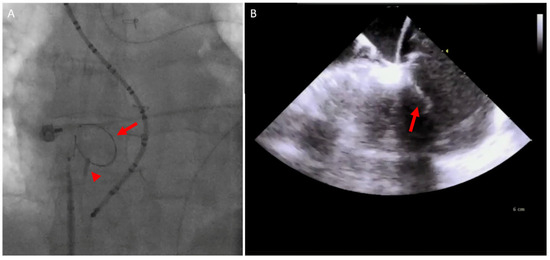

5.1. Paravalve Leak (PVL) Occlusion